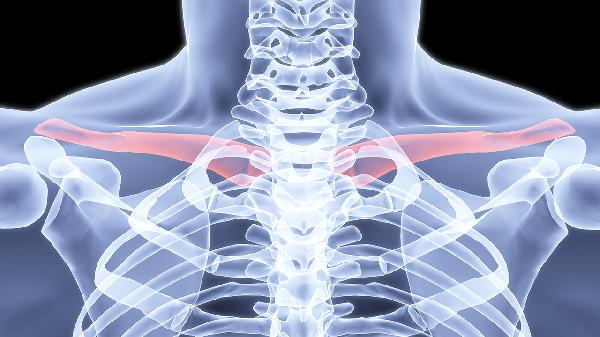

锁骨粉碎性骨折术后注意事项有哪些